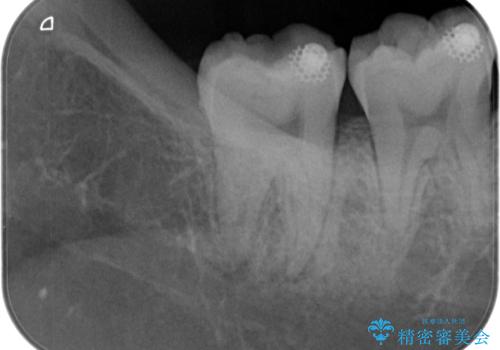

【根管治療】噛んだ時にしみる。最近になってズキズキ痛み、長引く痛みがある

担当医 河口智英